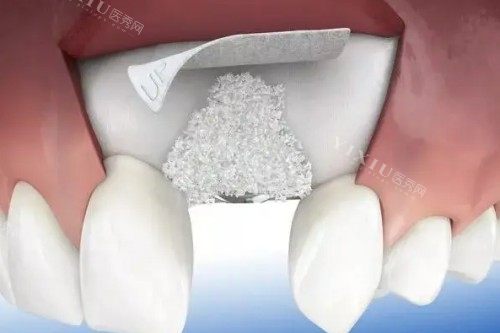

芜湖伊莱美口腔的智能化种植技术,依托新型的智能化设备与潮流技术。首先,利用 3D 口腔 CT 扫描仪,能够对患者口腔进行多角度、高精度扫描,获取牙槽骨密度、高度、宽度等关键数据,生成清晰、立体的三维模型。医生基于此模型,通过正规的种植设计软件,模拟种植过程,精细规划种植体的植入位置、角度和深度,大大提高手术的明确性。

此外,术中还运用智能化种植导板技术。种植导板就像是 “导航仪”,引导医生按照术前规划的方案,明确无误地植入种植体,减少手术误差,缩短手术时间,降低手术风险。这种智能化种植技术实现了从诊断、设计到手术的全程智能化、精细化,为患者带来更安心、有效的种植体验。

芜湖伊莱美口腔的智能化种植技术具备多方面优势。在精细性上,相比传统种植技术,它能将种植体植入误差控制在极小范围内,确保种植体与牙槽骨理想贴合,提高种植成功概率。同时,由于术前的精细规划,能够大程度地避开神经、血管等重要结构,减少术中出血和术后并发症的发生。